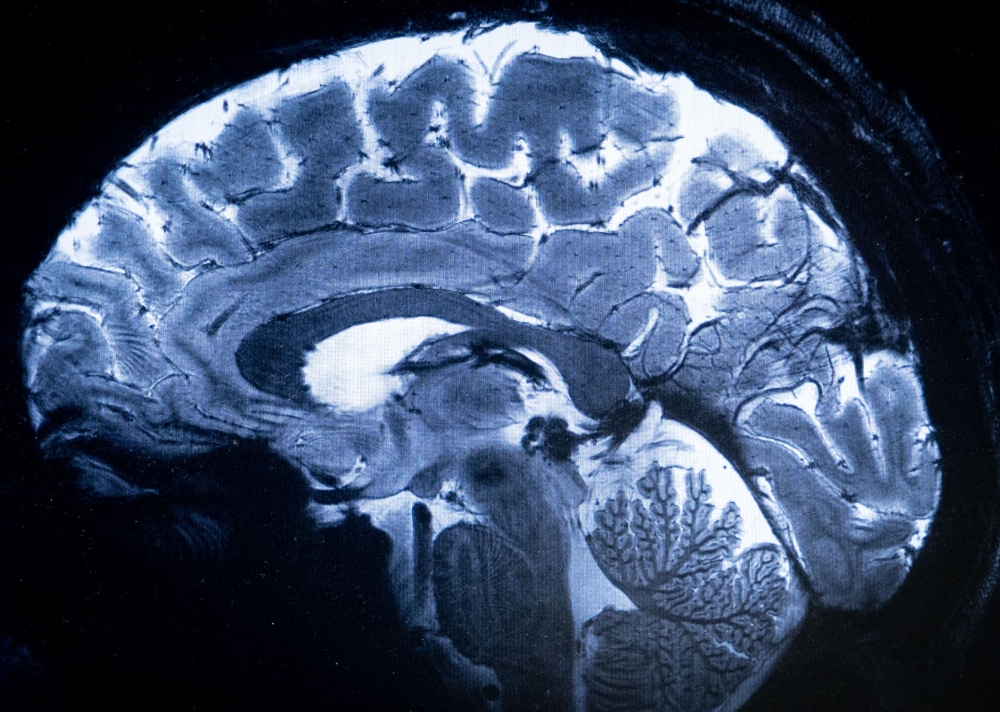

This image made with the Iseult Magneton 11.7 T MRI shows a brain during a magnetic resonance imaging (MRI) exam simulation at the Neurospin facilities in the Paris-Saclay Alternative Energies and Atomic Energy Commission. — AFP pic

The magnetic field created by the scanner is a whopping 11.7 teslas, a unit of measurement named after inventor Nikola Tesla.

This power allows the machine to scan images with 10 times more precision than the MRIs commonly used in hospitals, whose power does not normally exceed three teslas.

“With this machine, we can see the tiny vessels which feed the cerebral cortex, or details of the cerebellum which were almost invisible until now,” he said.